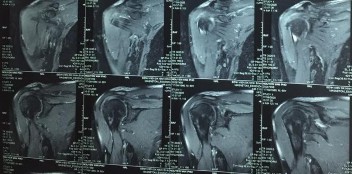

Hình phụ lục 2A: Phim CHT bệnh nhân trước mổ cho thấy rách lớn và co rút gân trên và dưới gai trên phim cắt mặt phẳng trán.

(Nguồn: BN nghiên cứu)